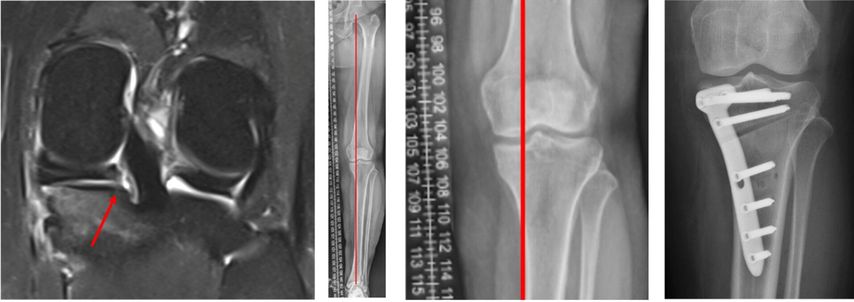

Risiko Meniskusriss mit Achsenfehlstellung

Abweichungen von der Beinachse und Verlust des Meniskus erhöhen beide gemeinsam das Risiko für eine Arthrose. «Wir haben speziell für Meniskusrisse bisher keine belastbare Evidenz, ab wann man die Beinachse operativ korrigieren sollte», sagte Behrendt. Eine Ausnahme scheinen Wurzelverletzungen zu sein. In einer Studie aus Seoul17 mit 476 Patienten, die wegen einer Pathologie am Innenmeniskus arthroskopiert wurden, hatten diejenigen mit Wurzelläsion eine deutlich ausgeprägtere Varusfehlstellung als Patienten mit anderen Rissformen (4,5±3,4° versus 2,4±2,7°). Orthopäden von der Mayo Clinic in Rochester18 empfehlen, bei Meniskuswurzelrissen nach einem Algorithmus vorzugehen (Abb.2). Viele Jahre wurde eine Achsenfehlstellung von >5° als korrekturbedürftig angesehen. Auf Grundlage einer Studie von 201319 und von Daten aus dem Knorpelregister der DGOU20,21 empfiehlt die Arbeitsgemeinschaft Klinische Geweberegeneration der DGOU, die Beinachse bereits ab einer Fehlstellung von 3° zu korrigieren.22 Eine Beinachsenkorrektur sei immer eine sehr individuelle Entscheidung, über die der Patient gut aufgeklärt werden müsse, sagte Behrendt.«Bei der Weiterentwicklung einer bereits eingetretenen Arthrose spielt die Achse einen sehr entscheidenden Einflussfaktor. Dies sollte grosszügig mit in das diagnostische Workup integriert werden.»